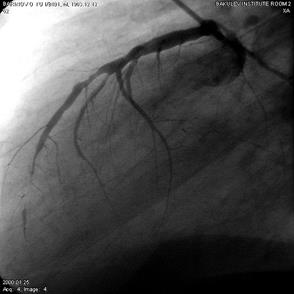

Коронарографическое исследование проводили на ангиографических установках "AngioscopeD" фирмы "Siemens" (Германия), "Integris 3000" фирмы "Philips" (Голландия) по методу М. Judkins и Sones. Для контрастирования КА использовали омнипак 300-350. КГ ЛКА выполняли в стандартных проекциях по методике Gensini: правая косая 150 и 450, левая косая проекция 600, левая боковая 900. В некоторых случаях использовали дополнительные проекции: левая передняя косая 450-750, каудокраниальная 300.КГ ПКА выполняли в стандартных проекциях: правой косой 450, левой косой 600, левой боковой 900 от сагиттальной оси. Анализ коронарограмм осуществляли на просмотровом аппарате "Tagarno 35AX". При анализе коронарограмм определяли тип кровоснабжения сердца, состояние основного ствола ЛКА, степень и уровень поражения коронарных артерий, диаметр коронарных артерий, количество пораженных артерий, наличие коллатерального кровотока.

Коронарография выполнена всем больным. Всем больным выполнена ангиография левой внутренней грудной артерии.